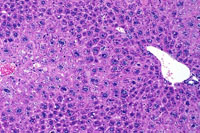

Centrilobular hepatocellular hypertrophy in a CD-1 mouse.

Centrilobular hepatocytomegaly (hypertrophy) in a mouse given phenobarbital for 8 months. Note the prominent eosinophilic cytoplasm reflective of smooth endoplasmic reticulum proliferation.